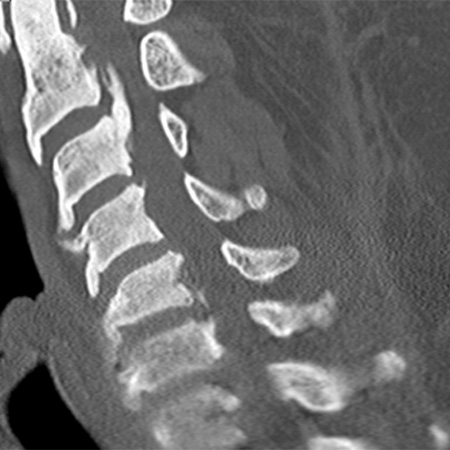

Posterior longitudinal ligament is a band of tough, fibrous tissue that supports and protects the spine. Ossification calcifies the ligament into a bony structure and leads to OPLL.

Medical imaging such as X-ray and MRI can help diagnose OPLL and inform the treatment plan. Current treatments range from pain and anti-inflammatory medication to surgery to decompress the nerves and spinal cord.